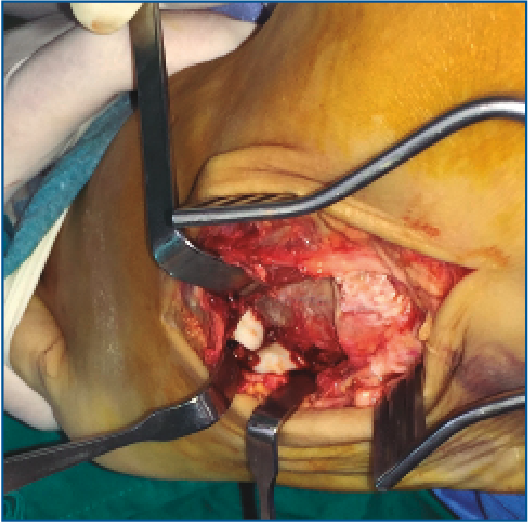

Es intervenido a la semana de la lesión realizándose, bajo anestesia raquídea e isquemia del miembro, una incisión dorsolateral desde la articulación calcaneocuboidea hasta la base del 4.º MTT. Se expuso el cuboides reflejando el extensor corto a dorsal y peroneo corto a plantar y se evidenció la desalineación del cuboides con el 4.º y 5.º MTT y el calcáneo creada por la luxación. Se realizó una reducción manual del mismo y una fijación con 2 agujas de Kirschner (agujas K) metatarsocuboideas, 1 aguja cuboideocalcánea y 1 calcaneocuboidea, realizándose al mismo tiempo una fijación de la apófisis lateral del astrágalo con un tornillo canulado (Figuras 3, 4 y 5). Se mantuvo 6 semanas inmovilizado, momento en el que se retiraron las agujas K. A la 6.ª semana, se inicia la carga con ortesis de carga hasta la 8.ª semana.

Figura 3. Abordaje quirúrgico longitudinal dorsal sobre el 4.º radio. Exposición del músculo extensor corto de los dedos.

Figura 4. Imagen intraoperatoria de la luxación del cuboides. Se visualizan las carillas articulares de la base del 4.º y el 5.º metatarsianos.